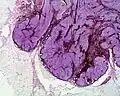

Micrograph of a blue nevus showing the characteristic pigmented melanocytes between bundles of collagen. H&E stain -